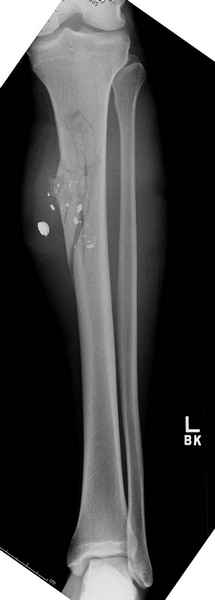

Re: Огнестрельный перелом бедра с дефектом кости.

Здесь несколько примеров из нашей практики:

2 перелом бедра